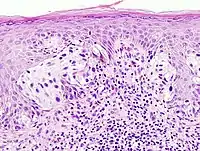

- Dermatopathology (A board-certifiable subspecialty in the U.S.)